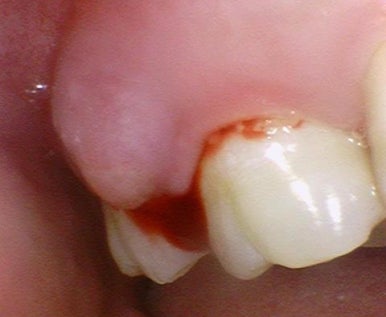

금이 깊은 것을 확인하고 발치 하였고

발치해보니 치아가 뿌리 일부까지 금이 가서

3덩어리로 나누진 상태였습니다.

발치 후 확인해보면 명확하게 치아가 쪼개져 있습니다.